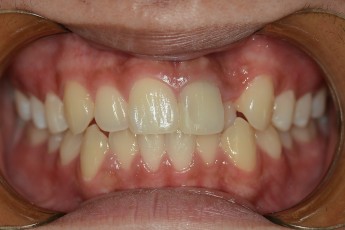

BEFORE & AFTER

- 덧니교정